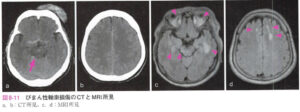

| びまん性軸索損傷 | 受傷直後より遷延する意識障害があるが、頭蓋内占拠性病変がみられないもの。MRIでは損傷部位がT2強調で急性期から高信号として描出される。![]() |

|

びまん性軸索損傷 DAI

| 病態 | 頭部への回転加速度衝撃による剪断損傷により、広範な白質神経線維の断裂が生じる病態。主に交通事故によるものが多い。過半数が死亡し、1/3が植物状態に至る。 |

| 症状 | 【受傷直後】 直後から強い意識障害: 【回復期】 高次脳機能障害:遂行機能障害、社会的行動障害、人格変化、認知障害など |

| 検査 | 【画像検査】 CT:明らかな頭蓋内損傷は認めない MRI:FLAIR像で脳梁・上小脳脚・脳幹の白質に小さな高信号領域の散在 |

| 治療 | 日常生活・社会生活への適応が困難となることから、リハビリテーション、生活支援などの確立に向けた取り組みが注目されている |